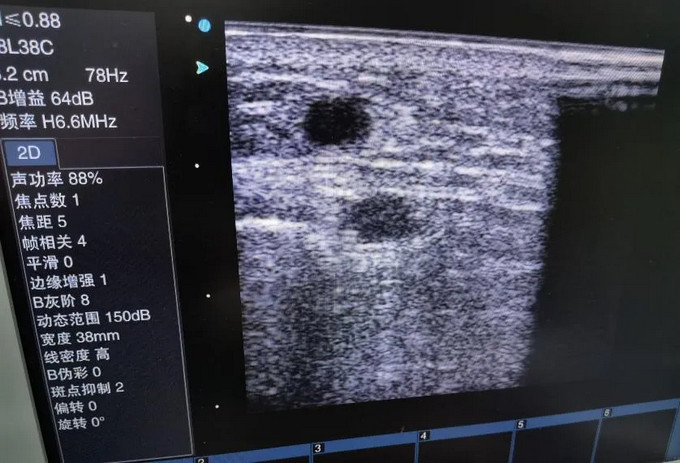

76歲的陸先生是福建中醫(yī)藥大學(xué)附屬人民醫(yī)院長(zhǎng)期血液透析病人,一直以右前臂自體內(nèi)瘺作為通路透析,最近透析時(shí)出現(xiàn)內(nèi)瘺血流量下降(透析時(shí)泵控血流量160ml/min) ,震顫明顯減弱,甚至不能維持血透需要。福建中醫(yī)藥大學(xué)附屬人民醫(yī)院腎病科血透室張文杰副主任醫(yī)師,李鵬飛主治醫(yī)師隨即對(duì)患者進(jìn)行床邊超聲檢查,發(fā)現(xiàn)患者動(dòng)靜脈內(nèi)瘺近吻合口處內(nèi)膜增生,伴管腔嚴(yán)重狹窄,最窄處僅1.5mm,如果不及時(shí)處理,很可能發(fā)生血栓導(dǎo)致內(nèi)瘺失功。因患者年齡較大,且合并糖尿病、高血壓、冠心病等多種基礎(chǔ)疾病,畏懼開刀手術(shù),張主任與患者及家屬溝通后,決定行超聲引導(dǎo)下內(nèi)瘺球囊擴(kuò)張術(shù)以挽救內(nèi)瘺,使之能繼續(xù)滿足透析要求。

手術(shù)前